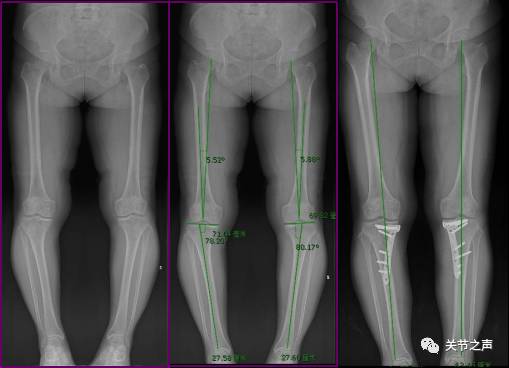

"重度o型腿"患者的新生

膝内翻(o型腿)的治疗

o型腿的治疗 - 好大夫在线

10°内翻畸形,膝关节轻度肿胀,双膝关节前内侧固定压痛点,膝关节rom